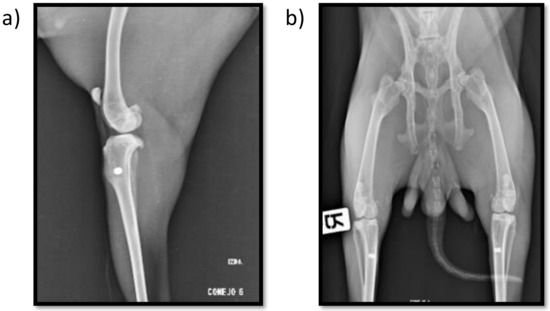

2.1. Clinical and Radiographic Results